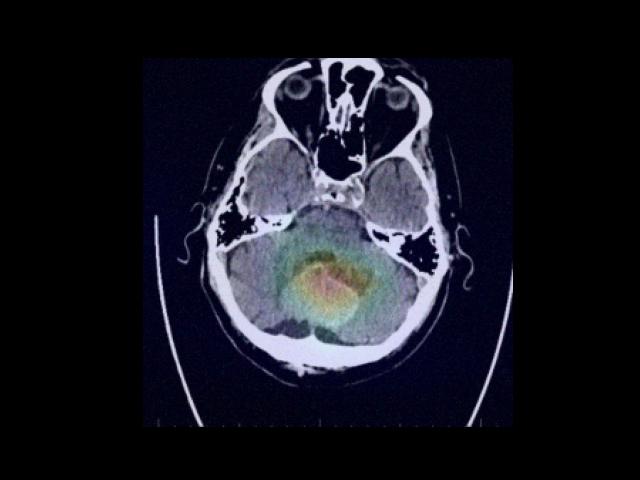

Sample Gallery